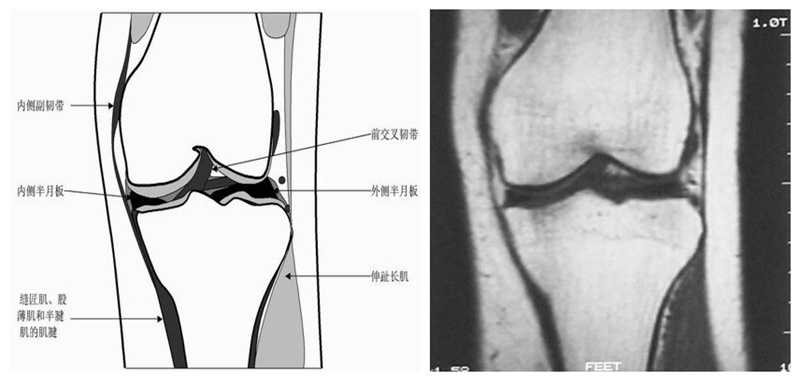

膝关节冠状面MRI解剖

显示内外侧副韧带、腘肌和拱状韧带,有无信号和结构改变,侧重关节胫股软骨的两边和半月板的体部。

冠状位解剖第二层